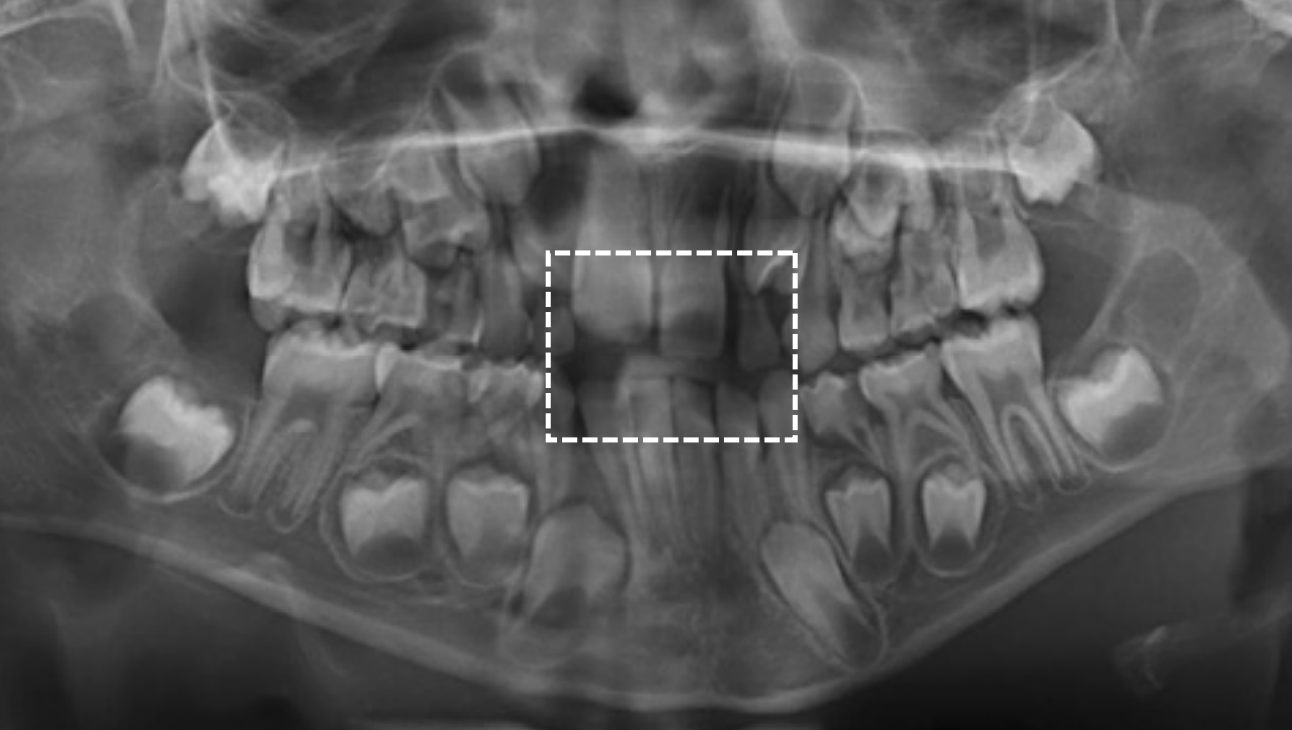

Dental age 9 the maxillary lateral incisors have been in place for 1 year, and

root formation on other incisors and first molars is nearly complete.

Teeth erupted Maxilla 12CDE6, Mandible 12CDE6

Teeth unerupted – Maxilla 3457, Mandible 3457

Dental age 11 is characterized by the eruption of the mandibular canines,

mandibular first premolars, and maxillary first premolars

Teeth erupted Maxilla 12C4E6, Mandible 1234E6

Teeth unerupted – Maxilla 3457, Mandible 57

Dental age 12 is characterized by eruption of maxillary canine and the maxillary and mandibular second premolars.

Teeth erupted– Maxilla 1234567, Mandible 1234567

Teeth unerupted – all 2nd and 3rd molars